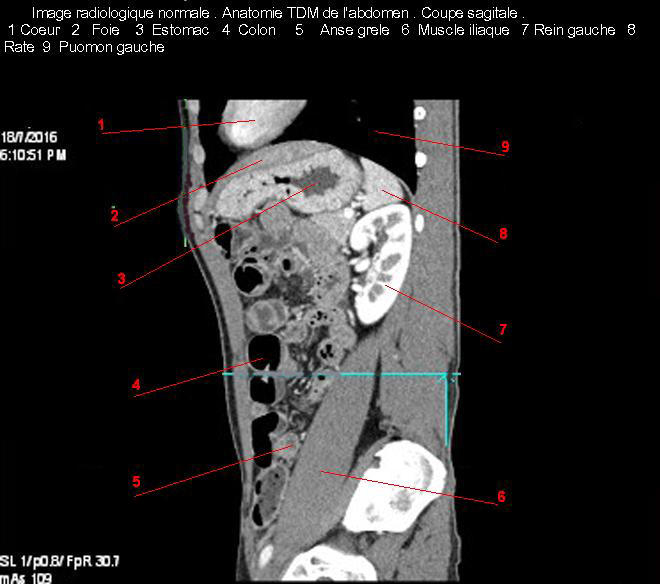

Images TDM de estomac en coupe

axiale ( Numero7) . Click ouvrie pour agrandir |

Et en coupe sagitale ( numero 3 ) . Click ouvrie

pour agrandir |